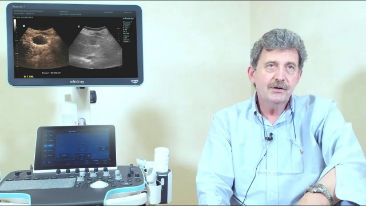

Resona 7

Desde que a empresa foi fundada, a Mindray est├Ī continuamente explorando novas maneiras de melhorar a confian?a no diagn├│stico. Alimentada pela mais revolucion├Īria tecnologia ZONE Sonography?, a nova plataforma Resona 7's ZST+ traz uma qualidade de imagem ultra-som a um n├Łvel superior por aquisi??o de zona e processamento de dados do canal.